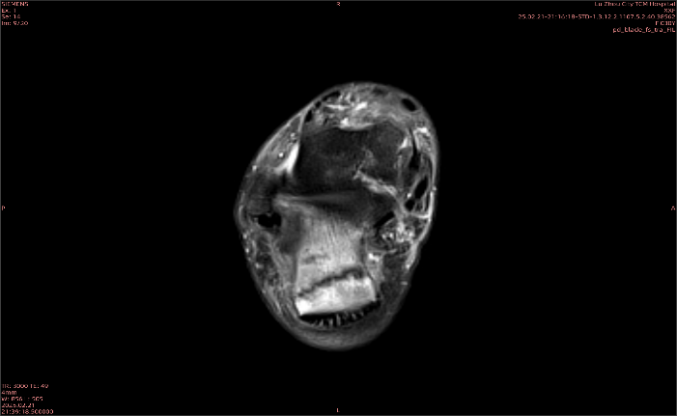

舉例圖像

圖1

專業(yè)解釋看不懂沒關(guān)系,大家看圖1和圖2就可以了,這是同一個患者跟骨的磁共振和CT圖像,圖1的紅色箭頭指示的黑線就是磁共振圖像顯示的骨折線,一目了然。而對比圖2的CT圖像上并未顯示異常。

這下大家明白了吧,如果懷疑隱匿性骨折優(yōu)先選擇磁共振檢查